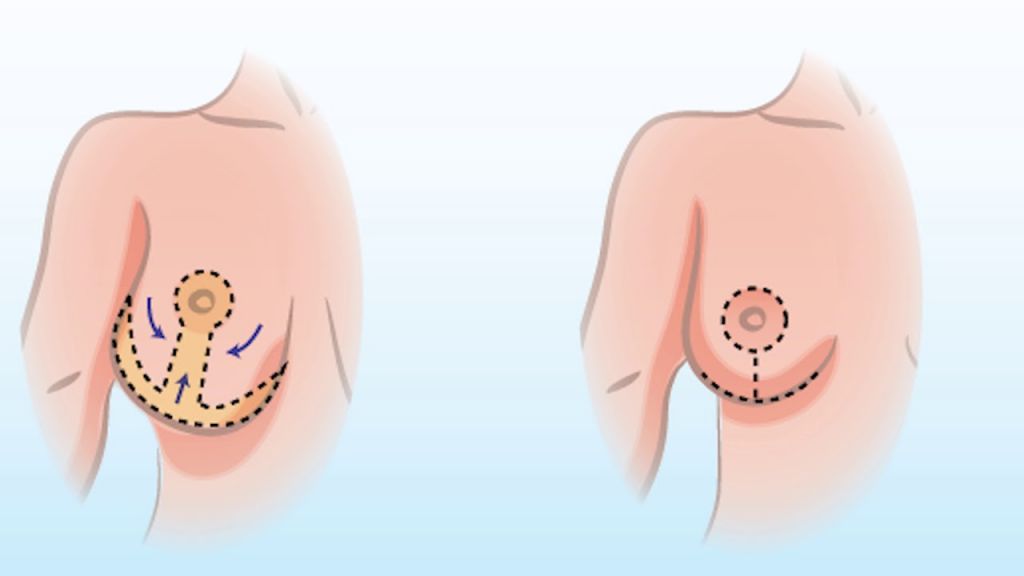

کوچک کردن سینه ماموپلاستی

ماموپلاستی یکی از انواع جراحی پلاستیک است که هدف آن تغییر سایز پستان (کوچک کردن سینه) بوده تا با تغییر فرم و کاهش سایز آنها به زیبایی اندام کمک کند بنابراین میتوان ماموپلاستی را یکی از انواع جراحی زیبایی به شمار آورد،گرچه در مواردي كه سينه خيلي بزرگ است و باعث مشكلات ساييدگي مهره هاي گردني مي شود،مي تواند درماني نيز محسوب شود.

رفع افتادگی سینه با لیفت سینه

یکی از شایع ترین مسائل زنان به خصوص در سنین بالا رفع افتادگی سینه است که این مورد می تواند با عمل زیبایی ماستوپکسی یا لیفت سینه بر طرف شود، در این مطلب از وب سایت...

بازسازی سینه در جراحی زیبایی سینه با پروتز

زمانی که عمل بازسازی سینه یا جراحی سینه صورت می گیرد هدف اصلاح نمودن تغییرات بدن و یا برگرداندن سلامتی به شخص می باشد. امروزه بسیاری از بانوان جهت درمان سرطان سینه به انجام جراحی سینه می پردازند ، در جراحی سینه بخش زیادی از بافت پستان حفظ می شود ، در جراحی سینه فقط بخش کوچکی از سینه را بر می دارند.